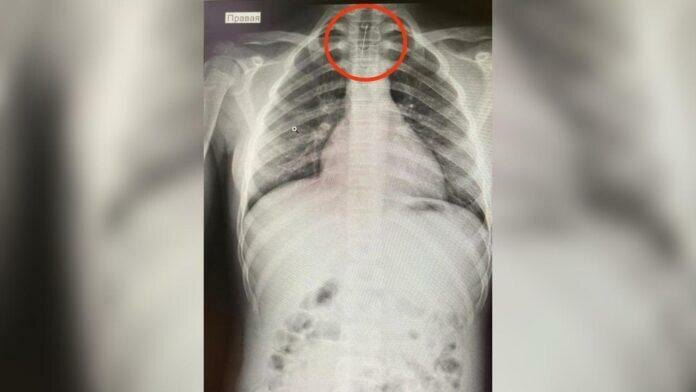

В Башкирии школьница едва не умерла, вдохнув иголку. Об этом сообщил главврач Баймакской ЦРБ Ильшат Рыскужин. По его словам, 14-летняя пациентка поступила с несколькими жалобами на боль груди, кашель и обильное слюноотделение. Было проведение медицинское обследование, в том числе ФГДС и рентген груди, в ходе которого обнаружили инородное тело.

Девочку доставили в РДКБ на скорой помощи. Врачи использовали метод бронхоскопии, позволивший аккуратно удалить иглу из трахеи, исключив серьезные последствия, сообщает "Мой Башкортостан".